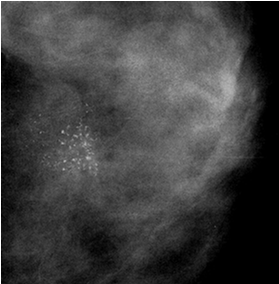

マンモグラフィ検査のご案内

当院では、乳がんの早期発見に効果的なマンモグラフィ検査を実施しています。特に従来の2D撮影に加え、より精度の高いトモシンセシスも導入し、皆様の健康をサポートいたします。

マンモグラフィ検査とは

マンモグラフィ検査は、乳腺専用のX線撮影です。一般的に片側の乳房につき、異なる方向から2枚撮影します。乳房を圧迫板で挟み、乳腺を平たく伸ばした状態で撮影します。圧迫することで診断に必要な鮮明な画像を得ること、乳腺の重なりを減らし病変を見やすくすること、放射線の被ばく量を低減することなどができるようになります。

トモシンセシスとは

Tomography(断層撮影)とsynthesis(合成)を合わせた造語で、3Dマンモグラフィとも呼ばれます。乳房を圧迫した状態で、様々な角度から連続的に撮影し、取得したデータを再構成して高精度の断層画像を表示する方法です。トモシンセシスでは乳腺の重なりを解消することができ、乳腺に隠れた病変の描出もしやすくなるため乳がんの発見率の向上や不要な再検査を減らすことが期待されます。

マンモグラフィ検査でわかること

・触ってもわからないような非常に小さな「しこり」や、悪性の可能性を示す「微細石灰化」といった異常を見つけるのに優れています。

・乳がんだけでなく、良性のしこりや石灰化も見つけることができます。

検査の対象者

国の指針に基づき、40歳以上の女性に対し、2年に1回のマンモグラフィ検査の受診が推

奨されています。マンモグラフィは乳がんによる死亡率を減少させる効果が科学的に証明

されている検査方法です。